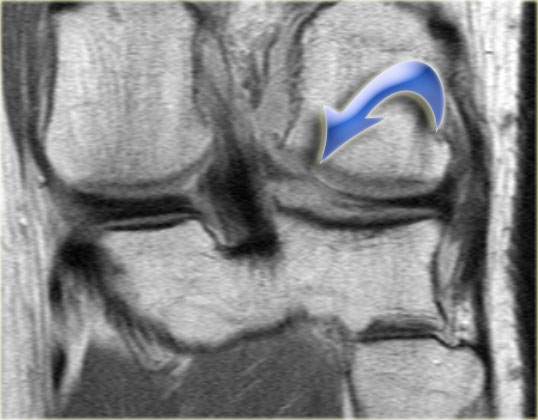

Bên trái là một trường hợp sụn chêm lật khác.

Lần này ở phía trong (medial).

Một phần sừng trước bị lật ra phía sau.

Chỉ một phần nhỏ của sừng trước được nhìn thấy ở phía trước.

Hầu hết các trường hợp sụn chêm lật xảy ra ở phía ngoài (lateral).

Dây chằng chéo trước (ACL) ngăn mảnh sụn chêm di chuyển hoàn toàn vào hố gian lồi cầu.

Trên hình ảnh mặt phẳng coronal, trước tiên sẽ thấy sừng trước to và phồng lên.

Ở phía sau sẽ thấy sừng sau rất nhỏ.